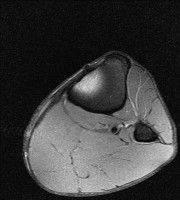

무릎 mri 간단히 봐주실 수 있으시나요 ㅠㅠ

안녕하세요 8년전 십자인대 수술하고 최근 무리한 운동에 무릎 불편감이 생겨서

mri 찍었습니다.

진단결과는 첫 찍은 병원에서 활액막염 이라는 진단을 받았습니다. 혹시 봐주실 수 있으실까요?

올라온 MRI가 단편적이라서 정확한 진단에 어려움이 있지만 십자인대에는 큰 이상이 있지는 않은것 같으며, 무릎관절내 물이 있는 것으로 보아 활액막염의 진단이 맞을 것 같습니다.

하지만 단편적인 영상이기 때문에 촬영병원에서 정확한 판독지 등을 받으시는 것이 좋겠습니다.